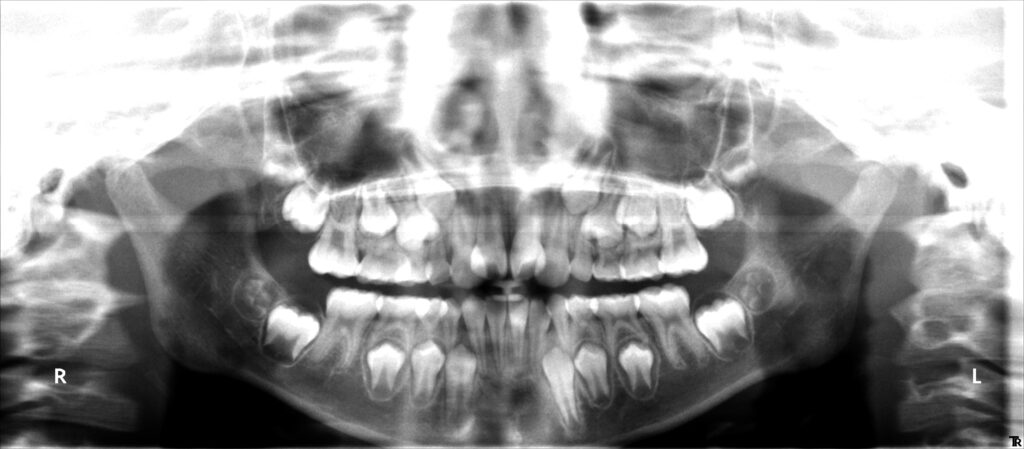

治療後2年

最後に高校1年の時に下顎前歯叢生(凸凹)予防のため、下顎埋伏親知らずの抜歯を行いました。後は、虫歯や歯肉炎にならないように、自己管理頑張ってください。